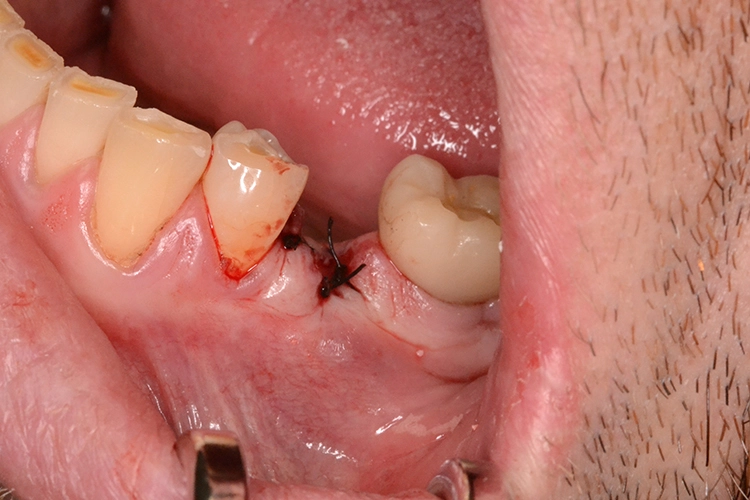

4. Sofortimplantation im Molarengebiet

Dr. Opitz

Aufgrund der Augmentation erfolgte die Freilegung 5 Monate postoperativ. Nach Ausformung des Emergenzprofils (Abb. 4i) erfolgte die definitive prothetische Versorgung durch eine okklusal verschraubte Einzelkrone (Abb. 4j).